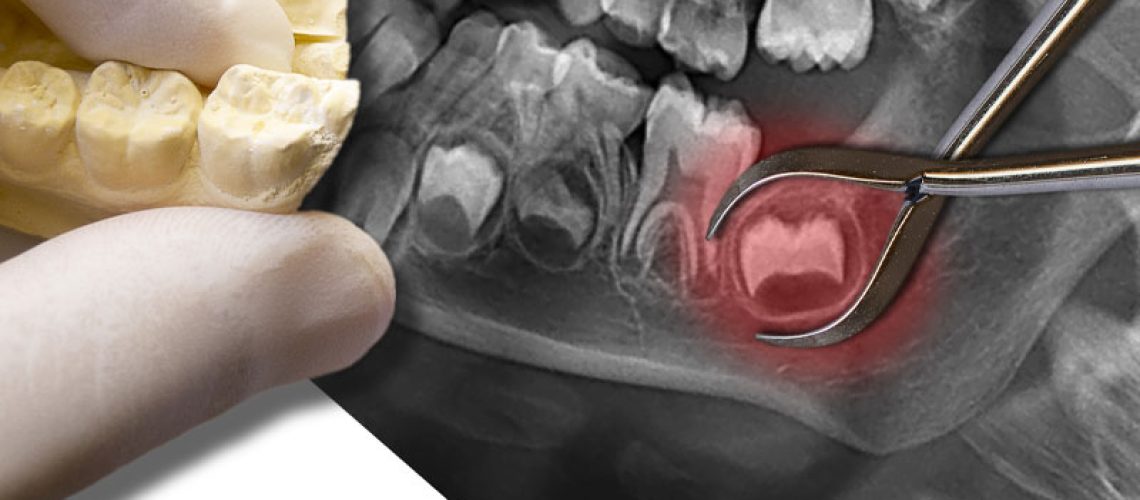

Impacted Wisdom Tooth XRay

Recovering after having your wisdom teeth removed isn’t known to be the most comfortable situation, but knowing how to get some sleep during this period can help you get back to normal more quickly. While sleeping after a wisdom tooth extraction can be difficult sometimes, there are a few things you can do to help yourself drift off into a peaceful slumber. Here’s a short list of a few ways to make it easier to sleep after having your wisdom teeth removed.